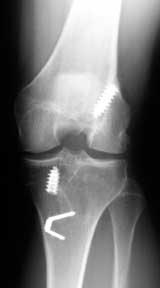

Improper placement of the ACL graft has been frequently cited as a cause of loss of knee motion. Grafts placed in what we call a “vertical orientation” as shown in the x-ray on the left can cause a limitation of knee motion. Unfortunately, if the limitation is severe and cannot be resolved with conservative rehabilitation measures, the graft has to be removed.

I place the ACL graft within the femoral and tibial footprint so that it occupies the central two-thirds or more of the footprint, to achieve an anatomic position (where the native ACL normally is found - see the x-ray on the right). To achieve this anatomic graft placement, sometimes a limited notchplasty is done to avoid a limitation of knee extension. I use the arthroscope to make sure that the graft position is exactly where I want it, and that there is no impingement of the graft against the lateral femoral condyle or notch when the knee is taken through the full range of motion on the operating table.